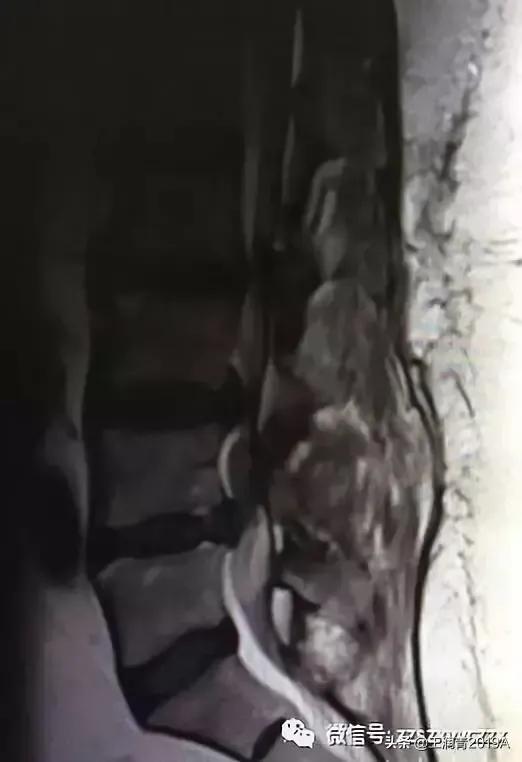

2、腰椎MR增强检查:平腰4椎体层面椎管内异常信号影,考虑腰椎间盘髓核脱出影(腰4-5)(图4-8)